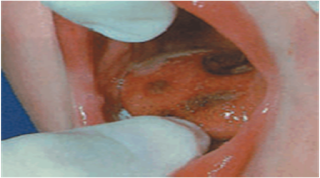

KİMYASAL YANIK

3. Derece yanıklar

Derinin tüm tabakaları etkilenmiştir.

Özellikle de kaslar, sinirler ve damarlar üzerinde etkisi görülür.

Beyaz ve kara yaradan siyah renge kadar aşamaları vardır.

Deri bütünlüğü bozularak açık yanık yarası oluşur.

Enfeksiyon olma olasılığı yüksektir.

Sinirler zarar gördüğü için ağrı yoktur.